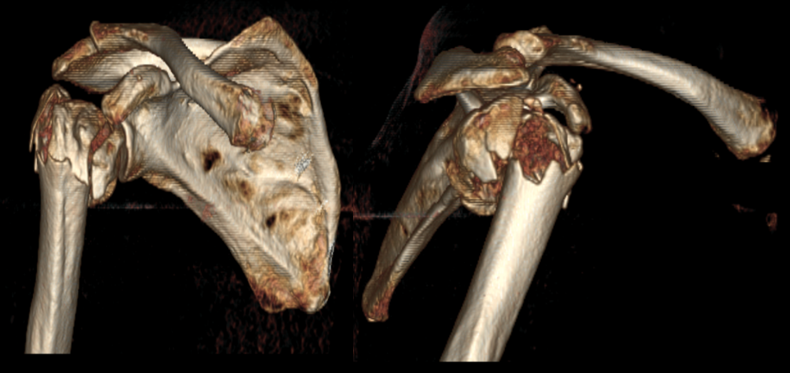

术前CT显示右肱骨近端粉碎性骨折、移位明显